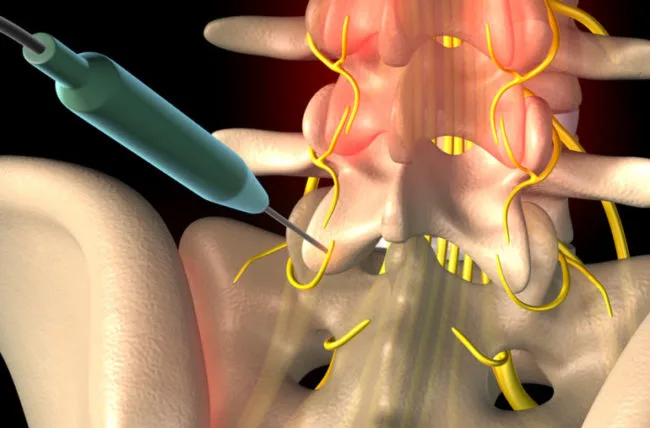

Hip fracture surgery may seem challenging, but it is considered a suitable treatment option for fractures in the hip area. The patient should see a doctor immediately to determine the appropriate treatment method and realign the fractured bones to their natural position. This can be done through either an incision in the hip area or by inserting screws or metal plates. Patients can typically leave the hospital after about two weeks, and complete recovery may take from 3 to 6 months.

Infections and wounds near the incision or injury site. Joint damage, as hip fractures can damage the cartilage surface of the joint. Injury to the sciatic nerve. If you would like to learn more about sciatic nerve injury and the development of sciatica, we recommend reading this article. The occurrence of something known as non-union, which is a rare problem. Anemia due to bone marrow damage. How Long Does Hip Fracture Recovery Take?

Hip fracture surgery can be scary for many people, and some may wonder if the bone returns to its normal state after the fracture. In reality, treating a hip fracture requires a surgical procedure, and the doctor may be able to realign the fractured bones after the break. This is done through a surgical procedure that involves proper fracture repair and stability of the bones using special plates. Therefore, hip fracture surgery should be performed under the supervision of a qualified surgeon after a comprehensive assessment of the case.